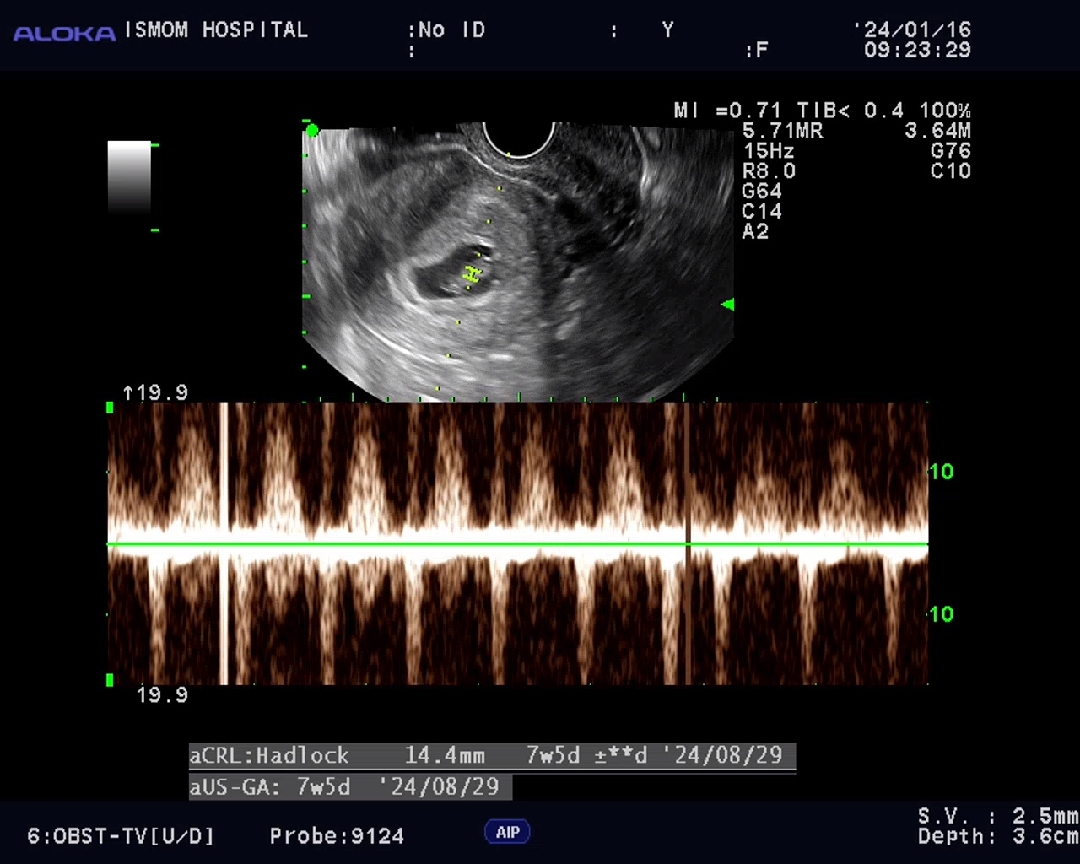

1.4cm되었어요ㅎㅎ

ㅎㅎ 1주일전까지만해도 3.7mm였는데 4배이상 컸네요!! 팔도 조금나오기 시작하구있어요ㅋㅋㅋ 신기방기~